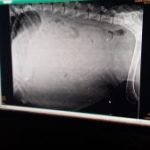

When using the OFA screening protocol. A breeder uses an X-ray in combination with an examination of the dogs history (blood line) to determine

If a certain dog may have genetic predisposition to hip dysplasia.

When the OFA scores a hip X-ray they are judging the laxity (looseness) of the hip for one particular dog. Joint Laxity is the determining factor that predisposes a dog to the development of hip dysplasia. Excessive laxity could be the result of traumatic injury, overloading of the joint by weight, lack of muscle strength, or adductor forces (e.g., bringing the legs together). But it could also be caused by a dogs genetics.

After a breeder receives an X-ray result that shows a poor score they then look at the test results of the of the parents grandparents and their offspring (the vertical pedigree) of the dog to see if there is a constant pattern of results that might help determine if they are dealing with a genetic component vs an environmental one for the dog affected.

The OFA test score only determines the laxity (looseness) of the hip. It is the breeders responsibility to determine if it’s caused by an environmental or genetic factor. The only way a breeder can determine if it is environmental vs. genetic is to compare it to the testing results of the parents, grand parents and their offspring (the vertical pedigree). There must be a substantial database to compare the OFA score to that allows the breeder to look for patterns of consistency that can help in this determination one way or the other. If there is a pattern of poor results in the vertical pedigree that would be a good indication of genetic components.

Ok here is where it gets tricky Lol. If your a breeder that has a dog with a fair – poor OFA score, that dog may still be a good breeding candidate. How is this? Ok say you have a dog that has a poor OFA score but upon the examination of the dogs vertical pedigree (parents, grandparents and all siblings) you see there is no evidence of hip dysplasia or poor scores whatsoever. Then chances are the dog in question suffers from an environmental cause of possible hip dysplasia not a genetic one at all. This means the cause (environmental) of his poor score and possibility of hip dysplasia will not be passed on to further generations. The vice versa is also true. If you’re a breeder that has a dog with a good OFA score but upon examination of the vertical pedigree there is a strong pattern of hip dysplasia and poor scores that dog will still not be a good breeding candidate simply because the chance of genetic issues are still strongly present.